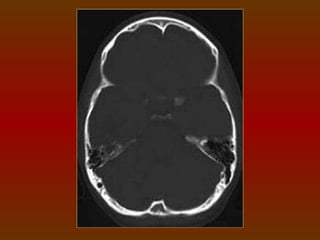

CORTE 3

a) Seios frontais

b) Goteira olfativa

c) Fossa hipofisária

d) Dorso selar

e) Tronco cerebral

f) Quarto ventrículo

g) Lobo temporal

h) Processo clinóide anterior